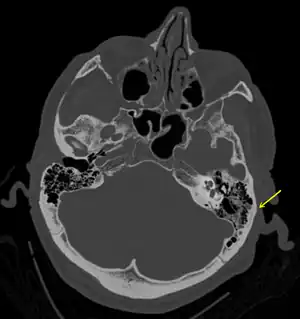

Fratura de crânio basilar

Este tipo de fratura normalmente exige um grau significativo de trauma para ocorrer.[1] A fratura é de pelo menos um dos seguintes ossos: osso temporal, osso occipital, osso esfenoide, osso frontal ou osso etmoide.[1] Eles são divididos em fraturas da fossa anterior, fossa média e fossa posterior.[1] Fraturas faciais também ocorrem frequentemente.[1] O diagnóstico geralmente é feito por tomografia computadorizada.[1]